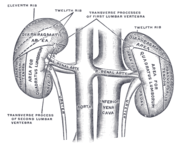

| 2. 5. 2011, 16:56 | Ledviny zezadu.png (soubor) |  | 40 kB | Webmaster | (Zdroj: http://en.wikipedia.org/wiki/File:Gray1123.png) | 1 |